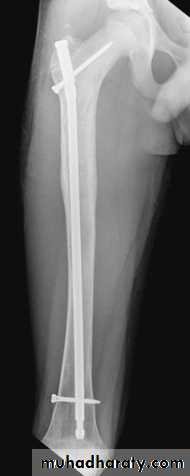

Definitive treatmentclosed fractures: by Open reduction and internal fixation, this will decrease the systemic complications.

fixation of femoral shaft fracture